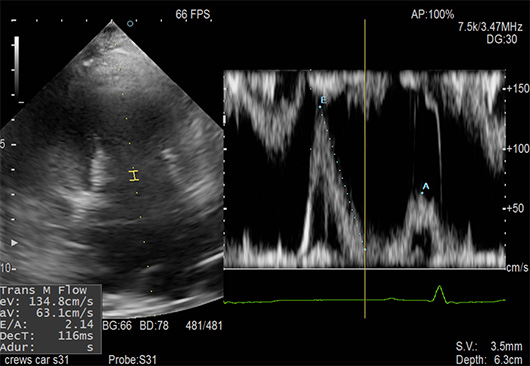

血流速度の測定(ドップラー検査)

心雑音が検出された場合は心臓のレントゲン・超音波検査による画像診断を行ってどのような心臓病なのか?どの程度の重症度なのか?を調べます。